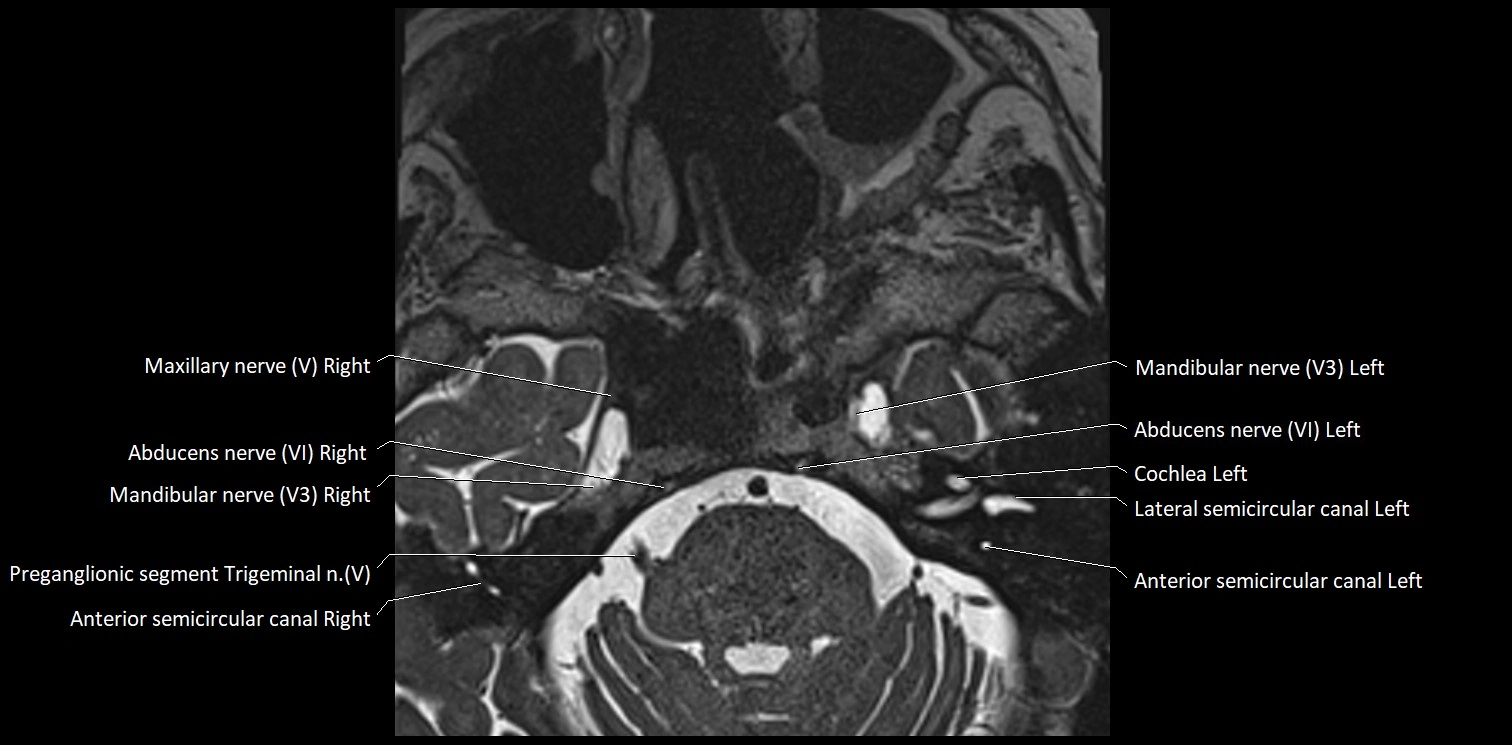

MRI Appearance

• The abducens nerve is a small, thin, linear structure

• Best visualized on high-resolution T2-weighted 3D MRI sequences (e.g., FIESTA or CISS)

• Seen as a hypointense (dark) line running from the brainstem at the pontomedullary junction, traversing the prepontine cistern, and entering Dorello’s canal under the petrosphenoidal ligament, then into the cavernous sinus, and finally the orbit

• May be challenging to visualize in standard MRI due to its small size

• Pathology may be inferred by absence, displacement, or enhancement of the nerve

MRI images

image